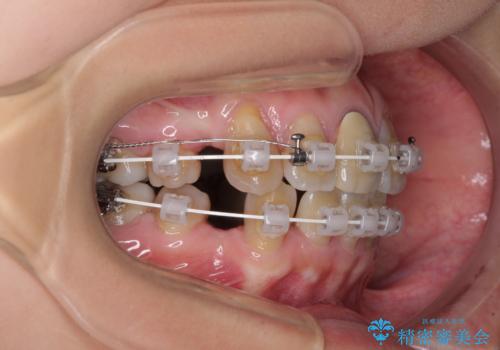

- 審美装置

- 2年5ヶ月

- 10-30回

上下の正中がずれていましたが、抜歯矯正であったので、極力正中位置を合わせるように治療を進めて行きました。

顎間ゴムの使用などにより、正中位置を改善することができました。